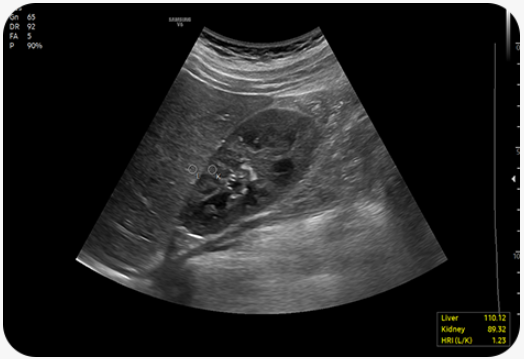

Hepato-renální index s automatickým doporučením ROI |

HRI™ (Hepato Renal Index) je index pro kvantifikaci steatózy jater na základě porovnání echogenity jaterního parenchymu a kůry ledvin. EzHRI™ umístí 2 ROI na jaterní parenchym a kůru ledvin a poskytne poměr HRI.